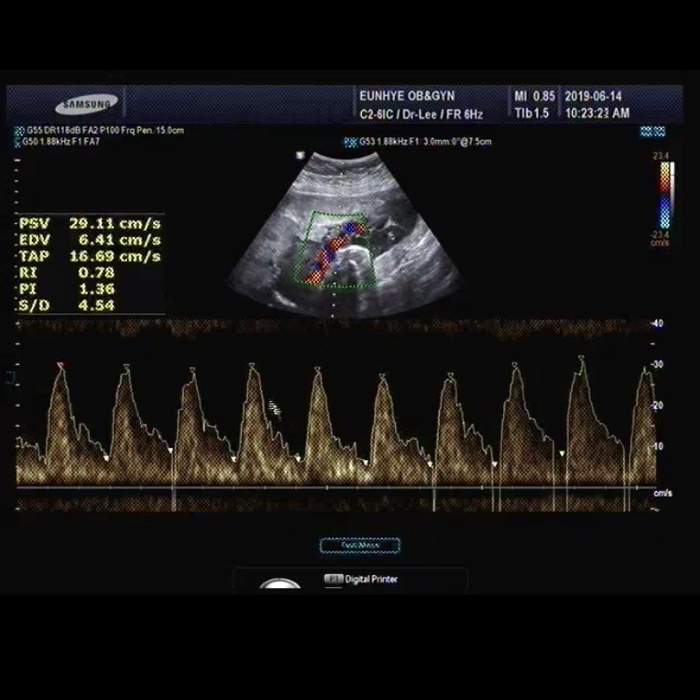

190614 임신32주 5일 / 두번째 입원

첫번째 삼성병원 입원은 19일만에 양수가 기적적으로 13cm로 늘고 염색체 검사도 이상없고 태동도 괜찮아서...

임신 25주, 양수과소증 진단 받다

4월22일 25주 0일 군산은혜산부인과 장원장님 25주 임당검사 140 간당간당하게 통과 정밀초음파를 보는데 ...